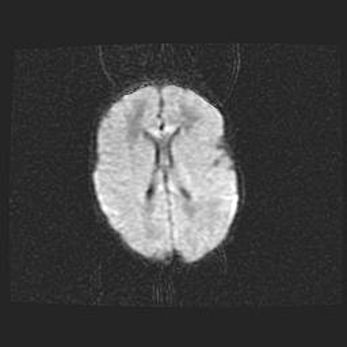

Неполная лизэнцефалия (пахигирия). Открытая гидроцефалия.

Возраст: 17 дней

Вес: 3110 г

Пол: мужской

Окружность головы: 33,5 см

Срок гестации: 35-36 недель

Лизэнцефалия—недоразвитие корковой пластинки и мозговых извилин в результате нарушения миграции нейронов коры. Поверхность мозговых полушарий гладкая. Микроскопически выявляется отсутствие нормальных слоев коры и скопление групп нейронов в подкорковом белом веществе.

Пахигирия—уменьшение числа вторичных извилин. В пораженном полушарии нервные клетки образуют толстый недифференцированный слой с неправильно расположенными нервными волокнами и группами гетеротопных клеток. Нервные клетки незрелые. Белое вещество истончено. При этом нередко аномально развит корково-спинномозговой путь.